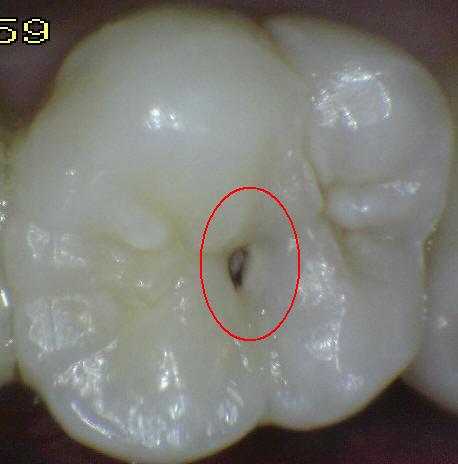

Código 3:

Ruptura localizada del esmalte debido a caries sin dentina visible

- El diente visto en estado

húmedo pueden tener una clara opacidad de caries (lesión de

mancha blanca)

y / o decoloración marrón de caries que es más ancha que la

fisura natural y la fosa, que no es consistente con la

apariencia clínica de esmalte sano. Una vez seco, se

observa una pérdida de estructura dental cariada en la

entrada, o dentro de la fosa o fisura . Esto se ve

visualmente como evidencia de desmineralización en la

entrada o dentro de la fisura o fosa, y aunque la fosa o

fisura puede aparecer sustancialmente más ancha que lo

natural, la dentina no es visible en las paredes o la base

de la cavidad ó discontinuidad .

-

En caso de duda, o

para confirmar la evaluación visual, la sonda de la OMS /

IPC / PSR puede ser

utilizada con cuidado a través de la superficie del diente,

para confirmar la presencia de una cavidad ( < 0,5mm.de

profundidad) al parecer limitada al esmalte . La

identificación de la cavidad se consigue deslizando el

extremo de la bola a lo largo de la fosa o fisura

sospechosa.